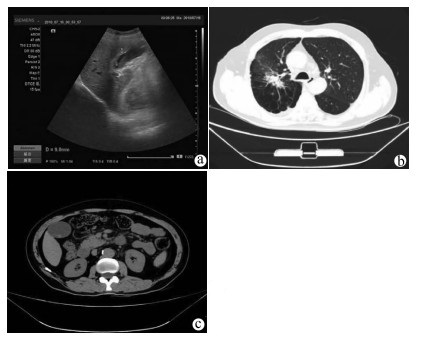

肝病超声诊断指南

中华医学会超声医学分会, 中国研究型医院学会肿瘤介入专业委员会, 国家卫生和健康委员会能力建设和继续教育中心超声医学专家委员会

2021, 37(8): 1770-1785. DOI: 10.3969/j.issn.1001-5256.2021.08.007

摘要(3138) HTML (6640) PDF (9311KB)(810)

超声检查无创、实时、价廉,无辐射、便于反复进行,是最常用的肝脏影像学检查方法。近年来,超声检查新技术如超声造影、弹性成像发展迅速,可有效鉴别肝内占位性病变性质、评估肝纤维化和门静脉高压程度以及监测肝病治疗效果,在临床肝病及其介入治疗中发挥重要诊断价值。本指南规范了肝病多模态超声技术(灰阶超声、彩色多普勒超声、超声造影、弹性超声)检查的仪器调置、患者准备及医生检查方法;对肝脏弥漫性病变(炎性病变、纤维化、硬化)、多种占位性病变及肝病介入操作的多模态超声技术诊断标准进行了定义和规范,同时推荐了超声监测周期及肝脏疾病超声诊断报告书写规范。